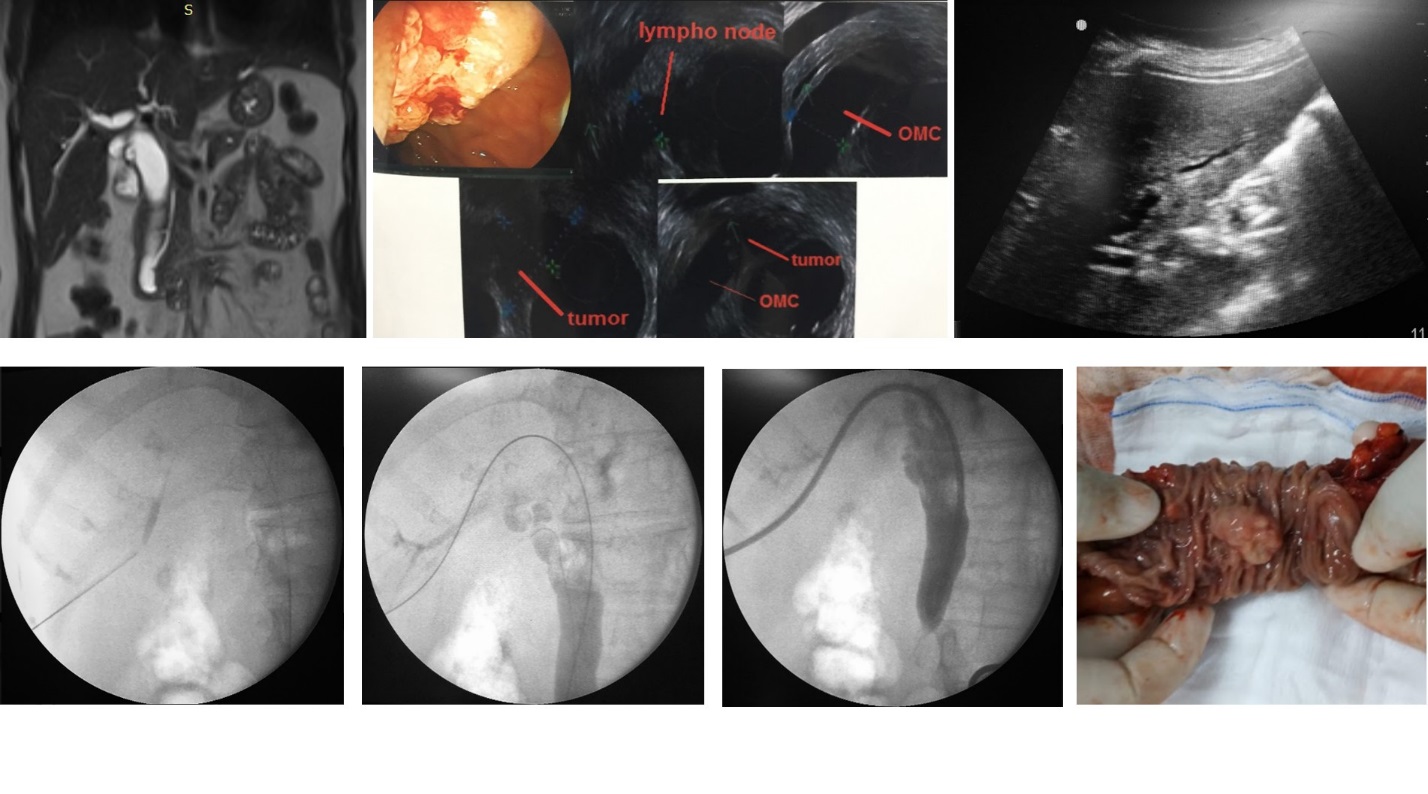

U bóng Vater gây giãn đường mật. PTBD giảm áp đường mật trước phẫu thuật cắt khối tá tụy.

Sỏi ống mật chủ gây shock nhiễm trùng đường mật/ hơi đường mật trong gan. PTBD cấp cứu. Bệnh nhân được phẫu thuật lấy sỏi sau đó.